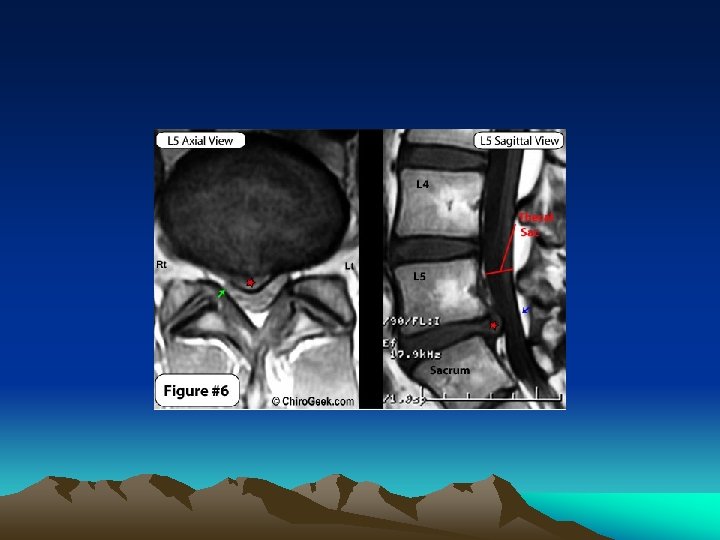

MRI • The gold standard for imaging of the herniated lumbar disc is magnetic resonance imaging

WHAT TO LOOK IN MRI

T-1 AXIAL VIEW

PROTON DENSITY IMAGE

ZONES OF ANTERIOR EPIDURAL SPACE / HERNIATION ZONES • Central region • Paracentral region or lateral recess • Intraforaminal zone or subarticular zone • Extraforaminal zone